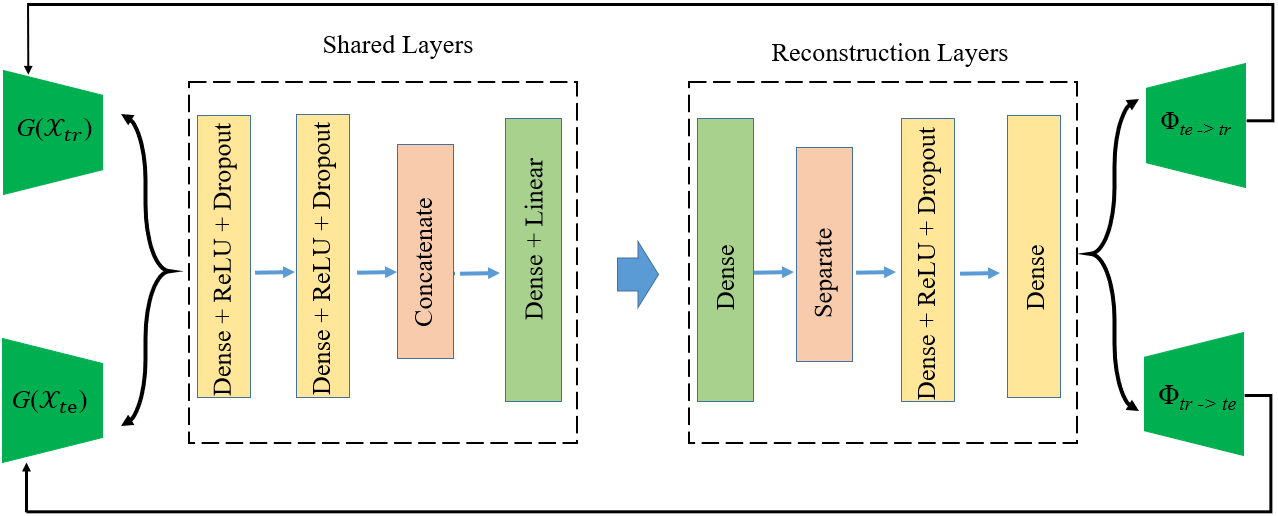

To encourage the training and test information to be preserved during the adversarial regression learning, we propose a feature reconstruction loss in our model. Details of the feature reconstruction layers are shown in Fig. 3; the reconstruction layers are right behind the shared layers, and it aims to reconstruct extracted features and maintain feature consistency during the conversion process without losing features. The feature reconstruction loss is defined as:

| (7) | ||||

where is the mean square error loss, which calculates the difference between true features and reconstructed features.